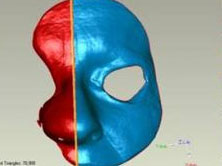

Winning the Battle Against Cancer

A patient had to undergo the surgical ablation of most of her nose because of a skin cancer that had attacked her right nasal septum.